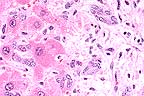

Moderate atrophy of bursal follicles accentuates the plical folds in a 5 week old chicken. (HE, 100X, 62K)

Gametocytes and trophozoites of Cryptosporidium baileyi lining the bursal epithelium of a 5-week-old chicken. (HE, 1000X, 22K)

Contributor's Diagnosis and Comments: 1. Moderate acute to subacute protozoan parasitic cloacal bursitis (Cryptosporidium sp.) 2. Mild lymphoid depletion - bursa of Fabricius. 3. Mild acute lymphoid follicular necrosis - bursa of Fabricius.

Multiple sections of the bursa of Fabricius were submitted. Moderate diffuse intraepithelial and superficial subepithelial accumulations of heterophils were evident. Mild acute lymphoid necrosis was noted within many of the bursal lymphoid follicles. Occasional intraepithelial cystic structures, many containing amorphous basophilic material and cellular debris, were also noted within the sections. Mild lymphoid depletion was also evident. Numerous round to ovoid basophilic structures measuring approximately 4-6 m, in diameter were noted adherent to the mucosal surfaces of the tissues.

AFIP Diagnosis: Bursa of Fabricius: Bursitis, acute, diffuse, mild, with surface- associated protozoa, broiler chicken, avian, etiology consistent with Cryptosporidium sp.

Conference Note: The contributor diagnosed lymphoid atrophy and necrosis of the bursa. The conference participants were unable to differentiate these changes from normal involution of the bursa without age-matched controls.